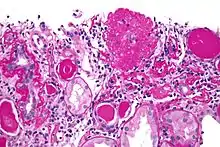

Light micrograph of focal segmental glomerulosclerosis, hilar variant. Kidney biopsy. PAS stain.

Micrograph of the collapsing variant of FSGS (collapsing glomerulopathy). A collapsed glomerulus is seen at the top, right-of-centre. PAS stain. Kidney biopsy.

Five mutually exclusive variants of focal segmental glomerulosclerosis may be distinguished by the pathologic findings seen on renal biopsy:[6]

1. Collapsing variant

2. Glomerular tip lesion variant

3. Cellular variant

4. Perihilar variant

5. Not otherwise specified (NOS) variant.

Recognition of these variants may have prognostic value in individuals with primary focal segmental glomerulosclerosis (i.e. where no underlying cause is identified). The collapsing variant is associated with higher rate of progression to end-stage renal disease, whereas glomerular tip lesion variant has a low rate of progression to end-stage renal disease in most patients. Cellular variant shows similar clinical presentation to collapsing and glomerular tip variant but has intermediate outcomes between these two variants. However, because collapsing and glomerular tip variant show overlapping pathologic features with cellular variant, this intermediate difference in clinical outcomes may reflect a sampling bias in cases of cellular focal segmental glomerulosclerosis (i.e. unsampled collapsing variant or glomerular tip variant). The prognostic significance of perihilar and NOS variants has not yet been determined. The NOS variant is the most common subtype. Collapsing variant is the most common type of glomerulopathy caused by HIV infection.